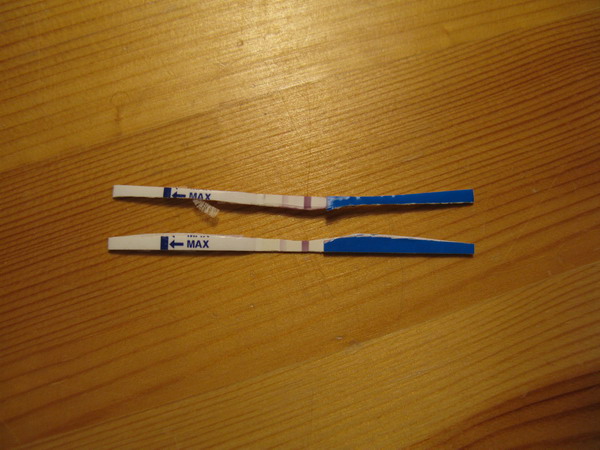

én csalok, és olvaslak a missed ab-ben is.

De ezt a csodás fotót szívesen nézegetem több helyen is!

kép

kép kép 2

kép 2